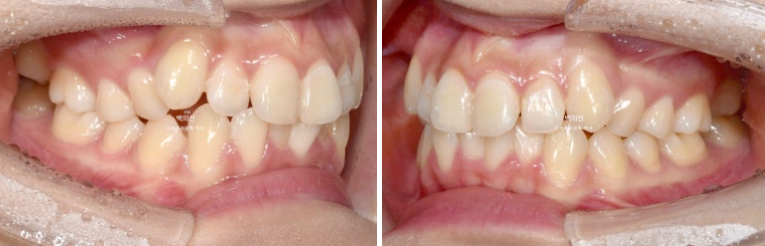

25.07

교합은 좌우 정 1급을 달성했으며 좋습니다.

좌 : 치료 전 / 우 : 치료 후